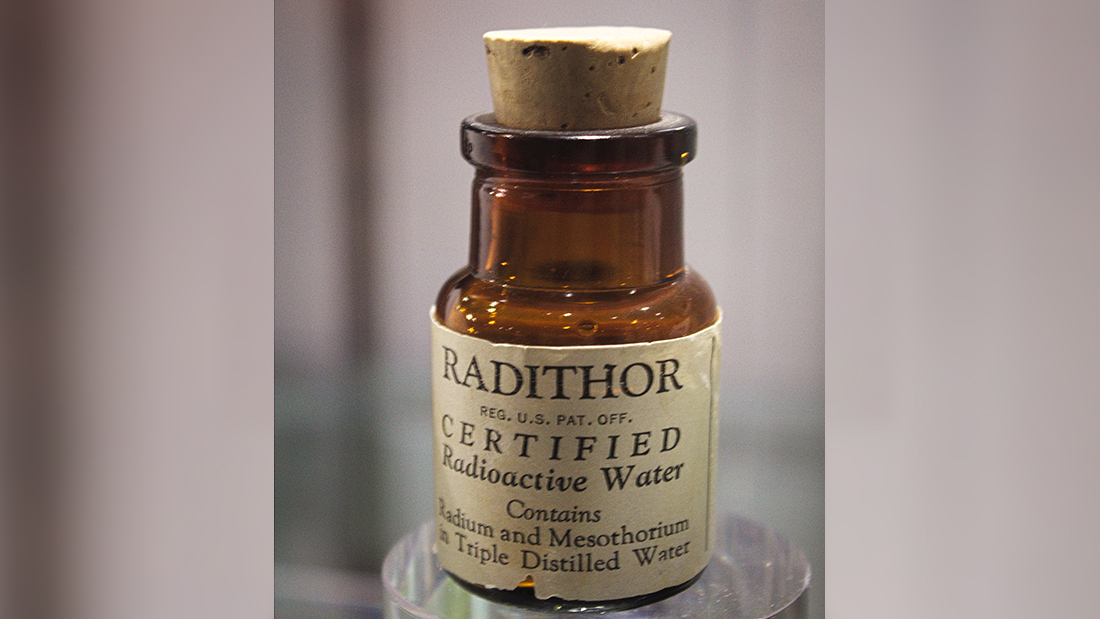

One such product became a favorite of American sportsman and socialite Eben Byers. Byers was a steel mogul and athlete that had himself a reputation of being a bit of a ladies' man, after winning the US amateur golf championship of 1906. In 1927, he fell off a bed on a train and injured his arm, which reportedly hampered him in both the athletic and sexual department.

His doctor prescribed him a drink called Radithor for his pain – likely because the inventor of the drink, William J.A. Bailey, offered doctors money for every drink they prescribed. Byers' pain cleared up (by coincidence or placebo) and he attributed it to Radithor, which was essentially radium diluted in water like cancer flavored Kool-Aid. From then on, he was convinced of the drink's benefits, and sent cases of the deadly juice to business colleagues, girlfriends and even fed it to his racehorses. For his own part, he drank 1,400 half-ounce bottles of the expensive drink.

At the time, he wasn't to know any better. Regulators were not convinced of harmful effects, and actually took action against one maker of radioactive "medicines" because they hadn't put in as many deadly radioactive materials as they'd promised.

After several years of necking radiation like it was going out of fashion (which it was, because of cancer) he began to lose weight, get headaches, and many of his teeth began to fall out. He told his doctor that he'd lost "that toned-up feeling", which is a fairly mild way of putting that your bones have begun to crumble.

In 1931, regulators began to wake up to the news that radiation is bad for you, and asked if Byers would like to testify at hearings. But by this point, he was far too sick, and instead, a statement was sent through his lawyer.

It relayed that Byers' "whole upper jaw, excepting two front teeth, and most of his lower jaw had been removed." As well as this, the lawyer reported, "all the remaining bone tissue of his body was disintegrating, and holes were actually forming in his skull."

He had only learned his case was terminal a few weeks before his death aged 51, by which point only six of his teeth remained. He was buried in a lead coffin.

Following his death, many other doctors (the real kind, not the ones who would prescribe deadly toxins for mild injuries) testified about the ill effects of radiation, leading in the end to the radioactive quackery industry.

The inventor of the drink, meanwhile, insisted that his drink was safe until his death of bladder cancer in 1949. When medical researchers exhumed his corpse 20 years later, his insides were "ravaged" by radiation and his remains were still warm.